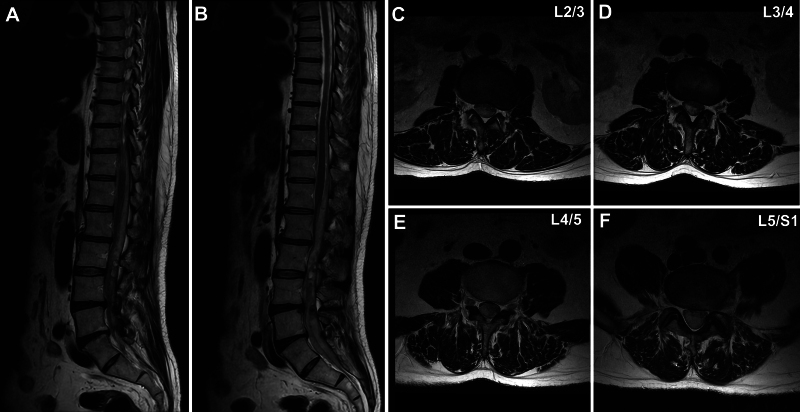

背景:脊髓硬膜外阻滞广泛应用于疼痛控制。虽然脑脊液渗漏或硬膜外血肿等并发症偶有报道,但硬膜外阻滞后的硬膜下血肿(SDH)是罕见的。据作者所知,涉及硬膜下和蛛网膜外腔的血肿以前没有报道过。观察:一名49岁男性,有慢性背痛病史,在常规腰硬膜外阻滞8天后出现严重的双侧腿感觉异常。MRI显示SDH从T8延伸至S3,压迫椎管背侧。通过L2-3和L5-S1半椎板切除术进行手术减压,随后行硬膜切开和Nelaton导管冲洗。患者术后症状完全缓解,3个月内血肿完全消退。经验教训:尽管脊髓硬膜外阻滞通常被认为是一种安全的手术,但罕见的并发症如SDH也会发生。对于硬膜外阻滞后未出现新的神经系统症状的患者,医生应高度警惕此类并发症。当诊断为SDH时,手术治疗包括椎板切除术和Nelaton导管冲洗可能是必要的,以优化患者的预后。https://thejns.org/doi/10.3171/CASE25448。

Observations: A 49-year-old man with a history of chronic back pain developed severe bilateral leg paresthesia 8 days after a routine lumbar epidural block. MRI revealed an SDH extending from T8 to S3, compressing the dorsal spinal canal. Surgical decompression was performed via hemilaminectomy at L2-3 and L5-S1, followed by durotomy and irrigation with a Nelaton catheter. The patient had full symptomatic relief postoperatively and showed complete hematoma resolution within 3 months.